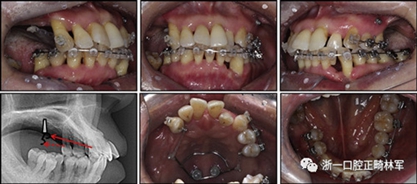

拔除下頜左側(cè)側(cè)切牙,除了4顆前牙外,下頜和上頜牙齒通過0.022英寸的Clippy-C裝置(日本東京的Tomy)粘接聯(lián)合。磨牙管粘結(jié)在下頜磨牙上。排齊過程從0.014英寸的鎳鈦弓絲開始,然后是0.016英寸的鎳鈦弓絲。為了美觀,在拔除的下頜左側(cè)側(cè)切牙間隙中放入一個修復(fù)體。為了防止牙齒的圓形轉(zhuǎn)動,4根上頜前牙被繞過,使牙齒能在尖牙被推向遠中后排齊。將兩個TADs(Orlus,Ortholution,Seoul,Korea)放置在腭板,并且有鉤子附著。將一小段0.016英寸的不銹鋼弓絲放置在上頜左側(cè)尖牙和前磨牙上,并且通過附著在腭板上的鉤子將上頜尖牙和左側(cè)前磨牙推向遠中。

對于近中傾斜和過度萌出的上頜右側(cè)尖牙,需要控制牙齒向遠中傾斜和向下推入。用兩個鉤子在兩側(cè)施加不同方向的力,以期望右側(cè)尖牙的推入(圖7)。在上頜尖牙遠中移動后,用一根0.014英寸的鎳鈦弓絲將4顆上頜前牙排齊。放置逐漸變硬的弓絲,直到上下兩個牙弓都放置0.017*0.025英寸的不銹鋼弓絲。然后關(guān)閉下頜前牙區(qū)間隙,用完全相同的力學(xué)原理將上頜全牙列向遠中移動,以獲得適當(dāng)?shù)母埠虾透采w。此外,還有一個0.017*0.025英寸β-鈦絲的直立彈簧應(yīng)用于下頜右側(cè)第二磨牙。當(dāng)直立彈簧接合到主弓絲上時,引起前磨牙的推入,第二磨牙的推出,前磨牙的頰側(cè)傾斜以及第二磨牙的舌側(cè)傾斜,以矯正牙弓形態(tài)(圖8)。

圖7. 用TAD將上頜牙齒推向遠中。兩個附著在TAD上不同方向的鉤子

圖8. 在主弓絲中的下頜第二磨牙的直立彈簧

由于患者有多個缺失的后牙,因此考慮到具有垂直方向的喪失。然而,她在拔除后牙后立即去正畸科就診。她封閉了天然的左側(cè)前磨牙,并且沒有前牙的咬合磨損。因此,垂直維度被維持是確定的。在正畸治療過程中,牙種植體植入在上頜后牙區(qū)和下頜右側(cè)第一磨牙的位置(圖9)。經(jīng)過3個月的骨結(jié)合后,種植體用臨時冠修復(fù)以支持垂直維度。

圖9. 上頜牙齒推向遠中,糾正下頜左側(cè)磨牙的傾斜度,并放入種植體